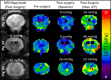

Methods: Baseline MRE measurements were obtained, and then catheters were surgically placed into the left and right lateral ventricles of three animals. ICP was systematically increased over the range of 0 to 55 millimeters mercury (mmHg), and stiffness measurements were made using brain MRE at vibration frequencies of 60 hertz (Hz), 90 Hz, 120 Hz, and 150 Hz.

Results: A significant linear correlation between stiffness and ICP in the cross-subject comparison was observed for all tested vibrational frequencies (P ≤ 0.01). The 120 Hz (0.030 ± 0.004 kilopascal (kPa)/mmHg, P < 0.0001) and 150 Hz (0.031 ± 0.008 kPa/mmHg, P = 0.01) vibrational frequencies had nearly identical slopes, which were approximately two- to three-fold higher than the 90 Hz (0.017 ± 0.002 kPa/mmHg, P < 0.0001) and 60 Hz (0.009 ± 0.002 kPa/mmHg, P = 0.001) slopes, respectively.